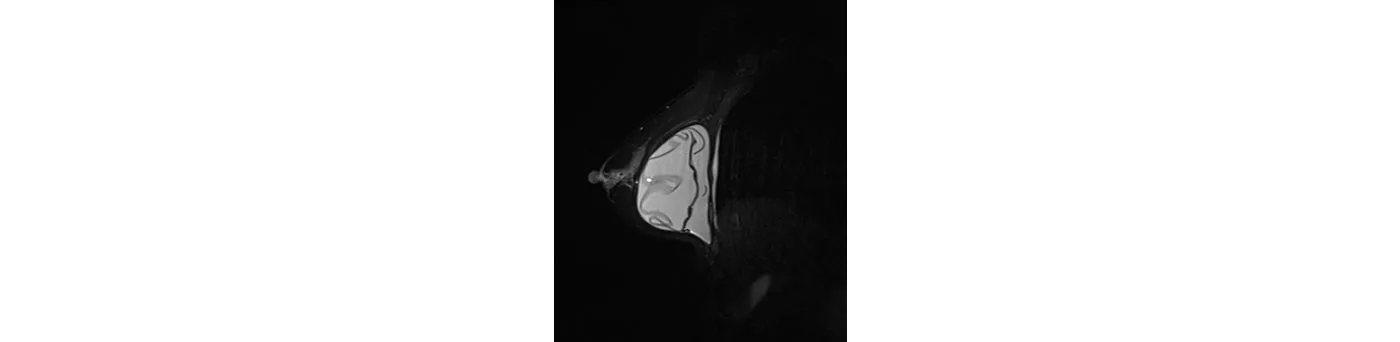

A 51-year-old female patient, 10 years after breast augmentation having regular examination. The MRI diagnosed a completely ruptured implant in the right chest.